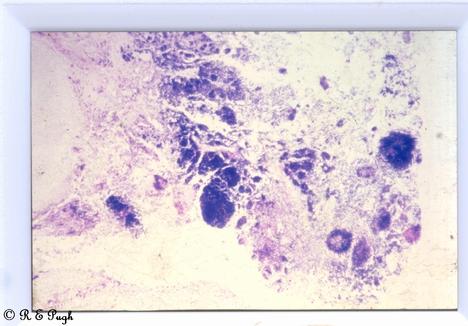

Sites: Subcutaneous Tissues

Actinomycosis in a chest wall sinus in an adult male in PNG. Gram Stain of Sulphur Granules.